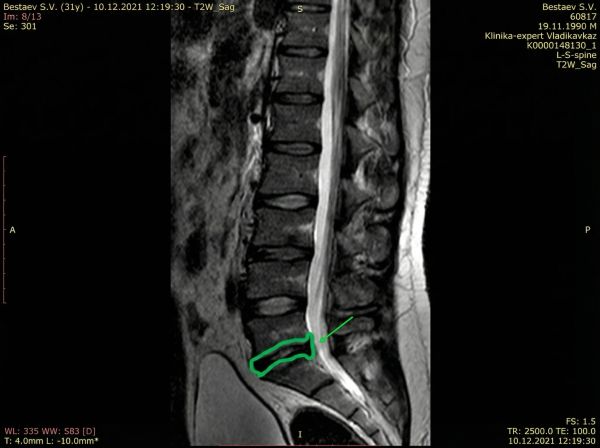

Один из 3170+ успешных случаев

Пациентка, 40 лет. Грыжа позвоночника, 2 сантиметра.

Грыжи нет, остался только рубец.